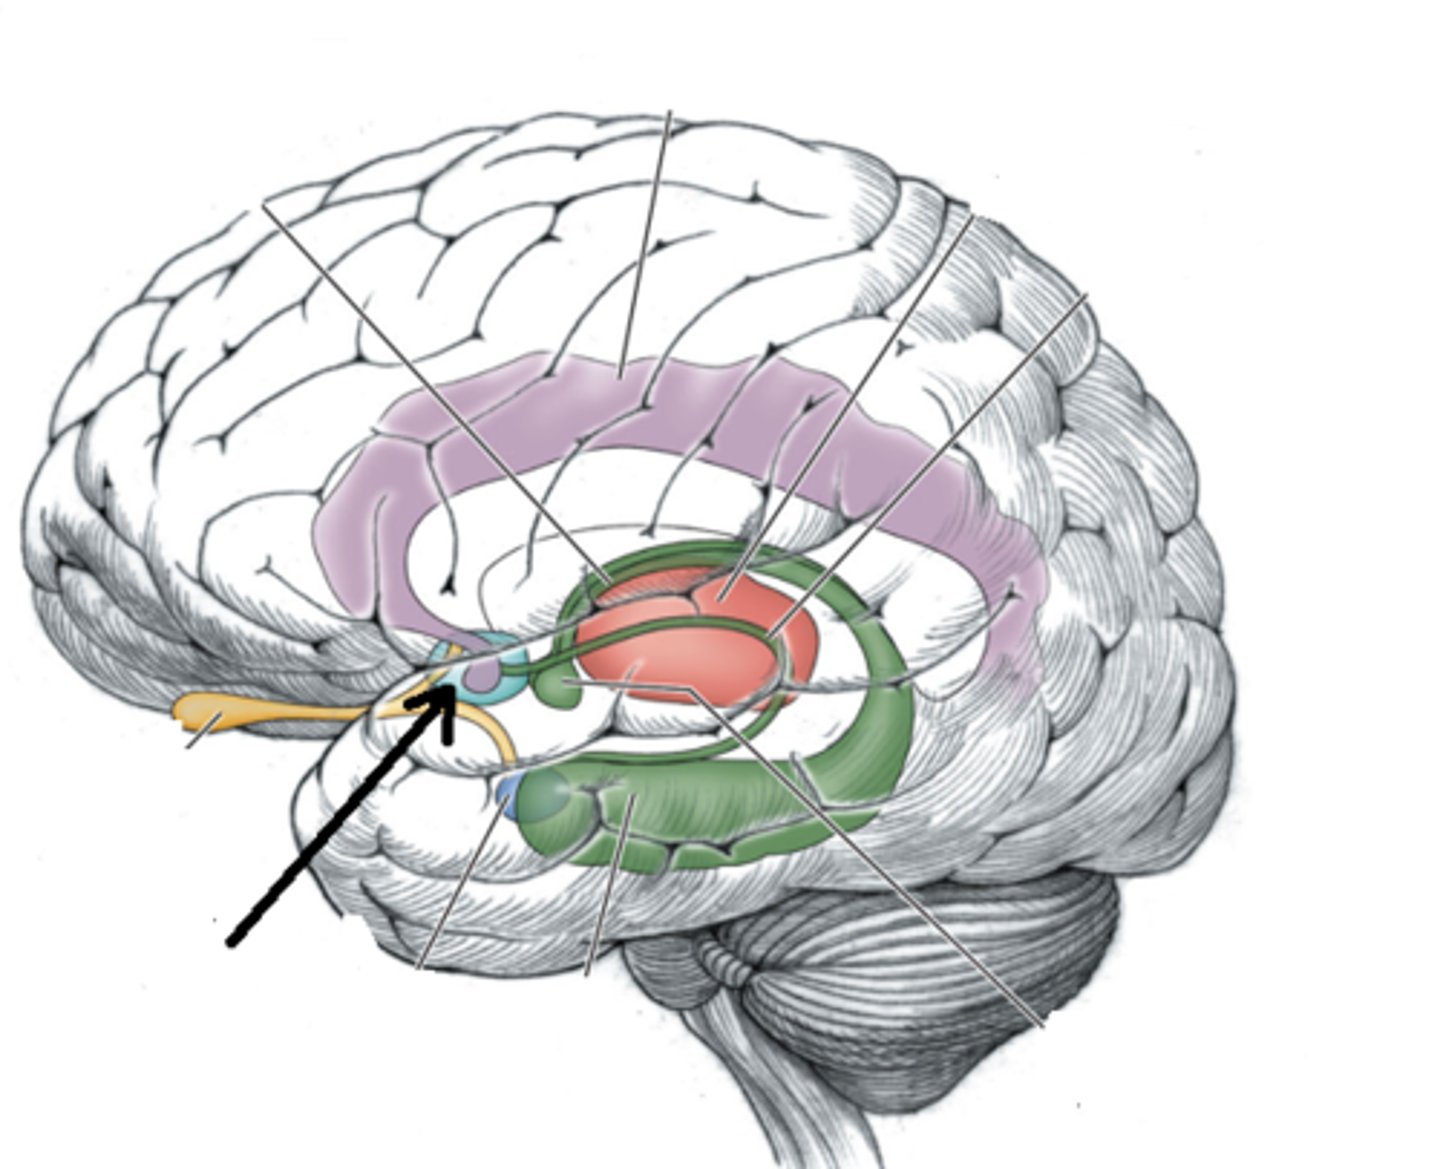

falx celebri

large, sickle-shaped, separates the cerebral hemispheres

tentorium cerebelli

2nd largest, crescent-shaped, separates cerebrum (occipital lobes) from cerebellum (arrow #5)

falx cerebelli

seperates the two hemispheres of the cerebellum. it lies inferior to the tentorium cerebelli, separating cerebellar hemispheres (arrow #7)

diaphragm sellae

smallest infolding covering pituitary gland & sella turcica